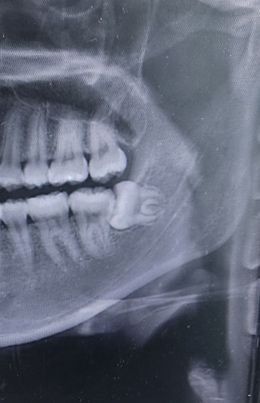

가로로 누워있는 사랑니 이게 신경에 닿아있는건가요?

사랑니가 신경에 닿아있는건지 뿌리가 신경에 닿아있는 것 같긴한데 맞나요..?? 이정도 사랑니면 국소마취하는건지 회복기간이 어느정도 되는지도 궁금합니다 대학병원갈 예정이긴합니다

문의주신 사진속 매복 사랑니는 난이도가 높은 사랑니로 신경손상의 우려도 있기에 대학병원이나 구강외과 전문의가 상주하는 치과에 방문하여 상태 확인후 발치를 하길 권합니다.

정확한 것은 ct를 찍어보아야 알 수 있습니다. 사랑니는 보통 국소마취로 발치를 진행하며, 회복기간은 사랑니의 매복 정도 등에 따라 상이합니다.

1. ct를 찍어봐야 정확히 알 수 있으나 아주 심하게겹쳐있는건 아닌 것 같습니다

1. 국소마취(부분마취)합니다

2. 회복기간은 초기치유는 1~2주정도, 온전히 아물기까지는 1~2달 잡으시면 됩니다

사랑니? 의 뿌리가 신경관과 가까이 위치하는 것은 맞습니다. 하지만 위험할 정도로 가깝게 위치한 것은 아닙니다. 기울어져 나있는 사랑니 발치의 경우에는 난이도가 높기 때문에 구강 외과 전문의한테 발치를 하는 것이 좋을 수 있습니다.

엑스레이 상으로는 신경과 가까워 보이긴 합니다. 정확한건 CT를 찍어보셔야될것같습니다.